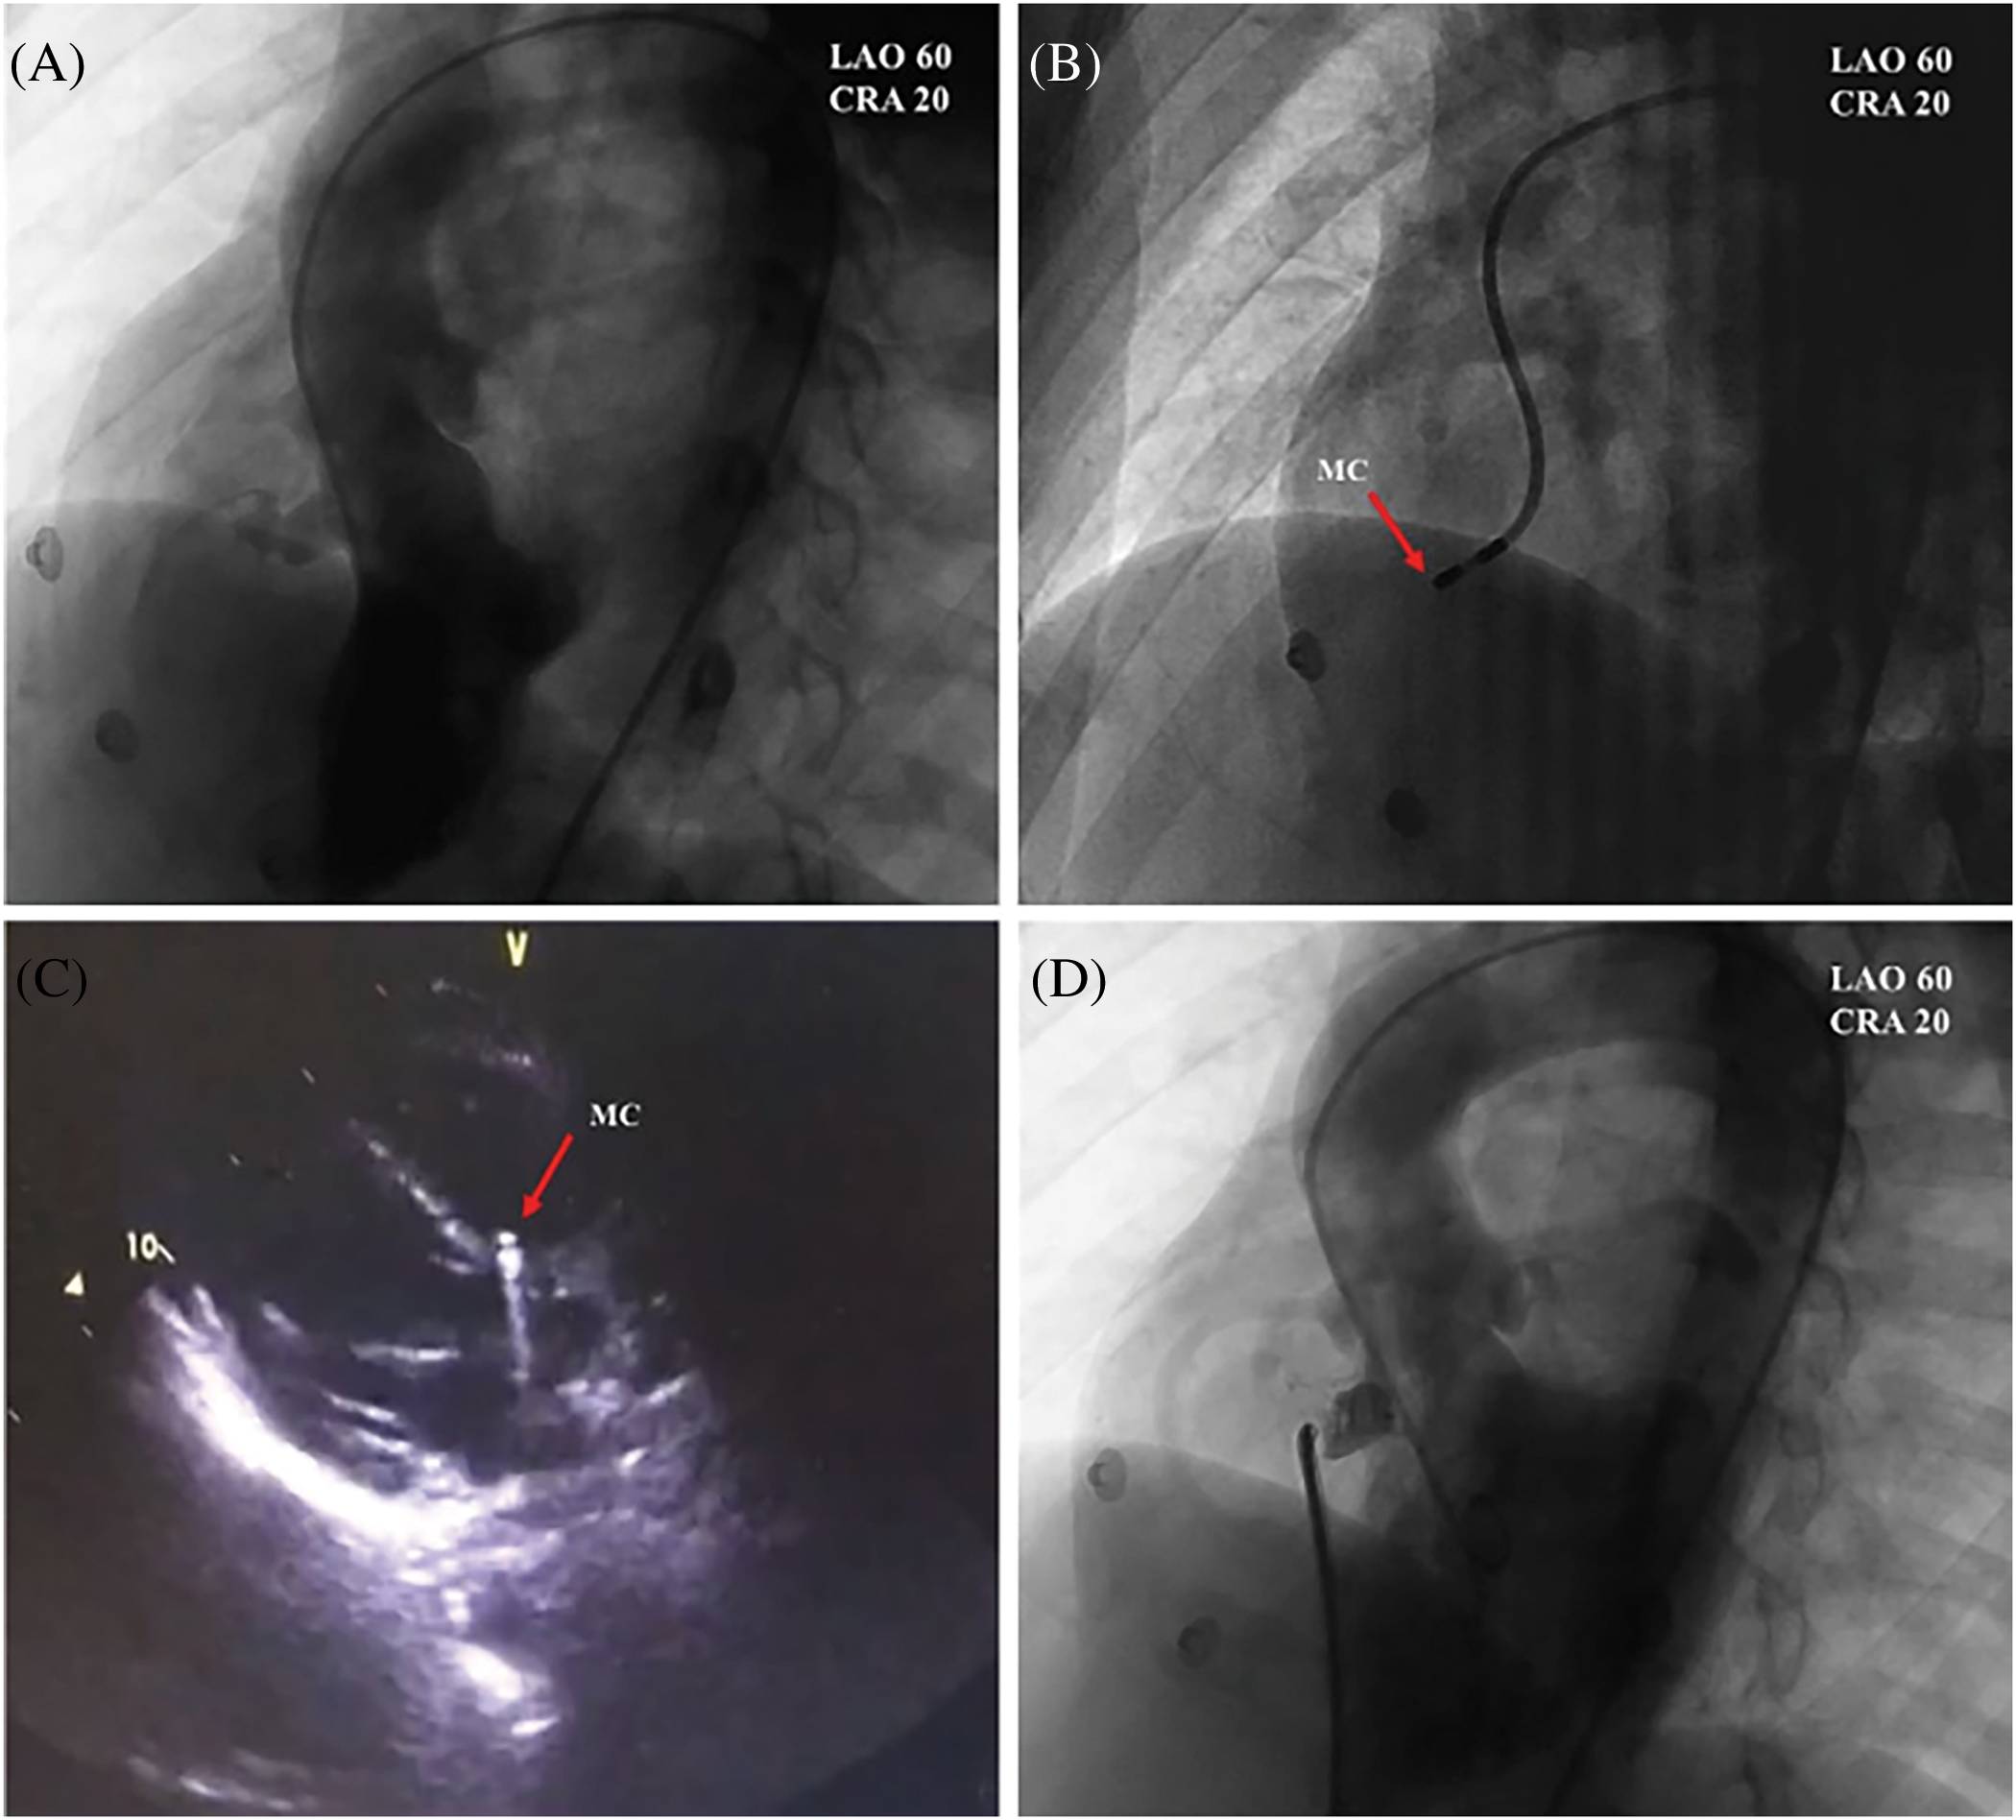

The patient was admitted one day before the procedure and underwent preoperative investigations, including urinalysis and complete blood count, liver and kidney function, electrolytes, coagulation parameters, ECG, chest X-ray TTE, etc. Informed consent forms were signed for interventional occlusion and the electrophysiological examination. The interventional treatment was detailed in the previous study [10]. Angiography of the left ventricle (LV) was performed to determine the PmVSD and the aortic valve (Fig. 1A). An occluder was selected based on the diameter of the PmVSD. A mapping catheter (NaviStar 4 mm; Biosense Webster, Diamond Bar, CA, USA) was utilized to conduct 3D electroanatomic mapping of the HPS in the LV (Fig. 1B). The location of the mapping catheter was also confirmed by TTE (Fig. 1C). To ensure that the aortic valve was not compromised, aortography was performed before releasing the occluder (Fig. 1D) [10]. The PmVSD site, the area of distribution of the HPS near the PmVSD, and the left ventricle were rapidly and accurately modeled point-to-point using the 3D electrophysiological scaler Carto system with a scaler catheter. The pacing was performed with different stimulation currents (20, 15, 10, 5 mA) and pulse widths (2, 1.5, 1, 0.5 ms) at the edge of the PmVSD and at the nearest area of the His-Purkinje system, respectively. The criteria for His capture were: 1. QRS wave width less than 120 ms; 2. QRS pattern close to subsinus pattern; 3. S-QRS close to subsinus HV interval. The morphology of the VSD under left ventriculography, the size of the defect, and the distance between the defect and the aortic valve were determined at the end of the marker test. Ventricular septal defect blockers and occluders made by Beijing Starway Medical Technology Incorporated Company (Beijing, China) and Shenzhen Lifetech Company (Shenzhen, China) were selected, each of which was divided into two types: symmetrical and small waist and large side type. If a high degree of atrioventricular block occurs intraoperatively or if a complete left bundle branch block is present, occlusion should be abandoned. The accuracy of the 3DEP/PmVSD map with the Carto system (Biosense Webster, Diamond Bar, CA, USA) is 0.1 mm (Figs. 1 and 2).

Figure 1: PmVSDs: transcatheter occlusion and three-dimensional mapping. (A) Identification of PmVSD using left ventriculography (LVG). (B) Mapping catheter (MC) placement within a pmVSD. (C) Transthoracic echocardiography verification of MC positioning at PmVSD borders. (D) LVG before the occluder releasing [10]